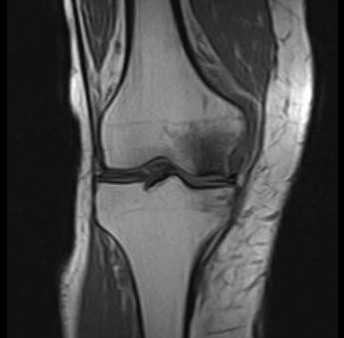

Болезнь Альбека: асептический некроз костей

![МРТ при некрозе костей колена. Нормальная ширина суставной щели, суставный хрящ ещё не поврежден. Отчетливое изображение некроза внутреннего мыщелка бедренной кости. © Prof. Dr. med. Sven Ostermeier]()

МРТ при некрозе костей колена. Нормальная ширина суставной щели, суставный хрящ ещё не поврежден. Отчетливое изображение некроза внутреннего мыщелка бедренной кости. © Prof. Dr. med. Sven Ostermeier

При недостаточном кровоснабжении костей погибают отдельные костные клетки. Таким образом некроз кости (Болезнь Альбека) означает потерю костного вещества в коленном суставе. Другими словами, остеонекроз — это отмирание костных структур.

Диагностика остеонекроза коленного сустава

Рентген проводится в любом случае. Однако видимые изменения в суставе можно установить лишь на прогрессирующей стадии болезни. Одним из главных сигналов Болезни Альбека на рентгенограмме является склерозирование - болезненное уплотнение костной ткани, которое возникает посредством перенагрузки коленного сустава.

На ранней стадии Болезнь Альбека можно диагностировать при помощи магнитно-резонансной томографии МРТ, которая показывает характерную, болезненную отечность. Измерение плотности костей необходимо для исключения остеопороза всей костной системы человека.